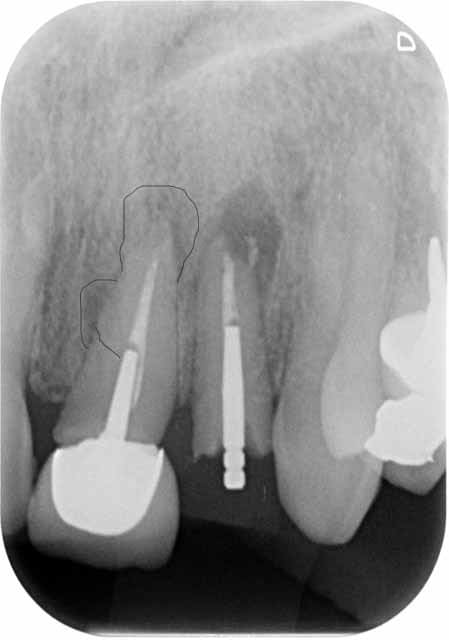

extraction, curetage lésion, implant 3.9 X 16, comblement des lacunes substitut osseux, vis de couverture.

02855 x 00000174 3 hdmbwk - Eugenol

02855 x 0000023a 3 sckpmy - Eugenol

02855 x 0000023b 3 kujdpz - Eugenol